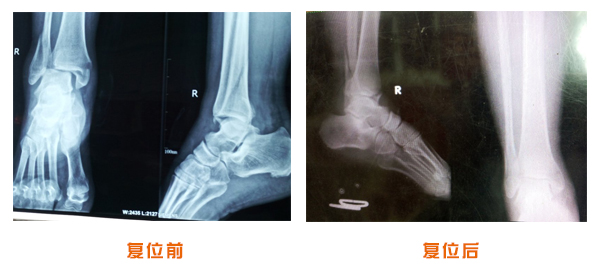

復(fù)位前后對比